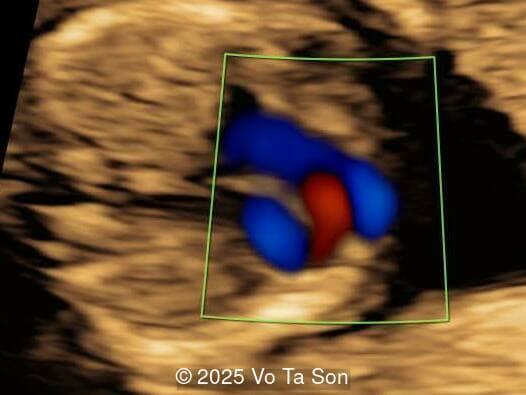

• Ventricular septal defect (VSD)

• Tricuspid valve regurgitation

• Right aortic arch